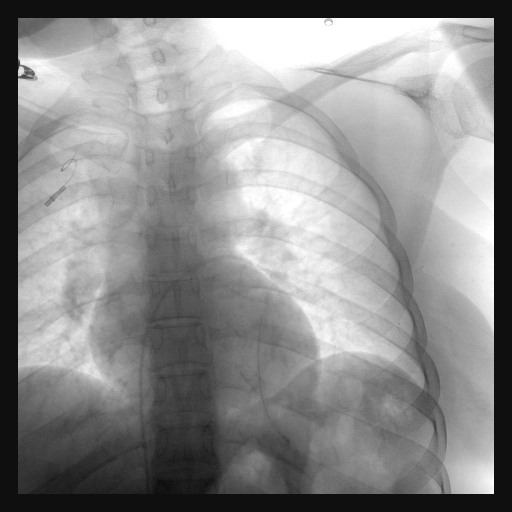

A twenty nine years old lady diagnosed as Carcinoma left breast underwent breast conservation surgery (pT2N2aM0, ER positive PR positive Her 2 neu positive) and presented for adjuvant chemotherapy. She was planned for adjuvant chemotherapy, radiotherapy and hormonal therapy as per standard guidelines. Chemoport reservoir was placed in the chest wall – right infraclavicular fossa and chemoport catheter was placed in the right subclavian vein. Post-procedure chest x ray revealed proper placement of the chemoport. She underwent first cycle of adjuvant chemotherapy with Docetaxel, Carboplatin and Trastuzumab without any complications. When she presented for second cycle (45 days after chemoport insertion), she was asymptomatic. However, there was no backflow of blood from the chemoport reservoir. Chest X ray revealed fragmentation and embolization of chemoport catheter. ECG showed normal sinus rhythm. Non Contrast CT scan chest was done, which revealed that the distal fragment of chemoport catheter had embolized to left pulmonary artery lower lobar branch, having migrated across the right atrium, right ventricle, main pulmonary artery and its left branch (Figure 1). After informed consent, retrieval of distal fragment of chemoport catheter was done in cath lab under local anesthesia under fluoroscopic guidance by Interventional Radiology team. It was retrieved from left pulmonary artery lower lobar branch in a procedure lasting forty minutes. The right femoral vein was punctured, 10 Fr Cordis sheath was introduced into the femoral vein, left pulmonary artery was cannulated using cobra 5 Fr catheter and then it was exchanged with snare over the guide wire. The left posterior inferior branch of pulmonary artery was selectively cannulated using Terumo guide wire and Cobra catheter. The tip of the foreign body was snared using Sequre snare system (4Fr, 10mm) and pulled through the pulmonary artery (Figure 2). The length of the catheter fragment was 4cm (Figure 3-9). The next day, chemoport reservoir and the proximal fragment of chemoport catheter was retrieved by surgery under local anesthesia. Patient tolerated both procedures well and was discharged on the third day.

Figure 4 Fluoroscopy image showing snare catheter in left pulmonary artery with foreign body in left pulmonary artery branch.

Figure 5 Fluoroscopy image showing snare catheter adjacent to the foreign body in left pulmonary artery branch.

Figure 6 Fluoroscopy image of Catheter pulmonary angiogram showing the foreign body in left pulmonary artery branch.

Figure 7 Fluoroscopy image of Catheter pulmonary angiogram showing foreign body as a filling defect in the lower lobar branch of left pulmonary artery.

Figure 8 Check fluoroscopy image after removal of foreign body.